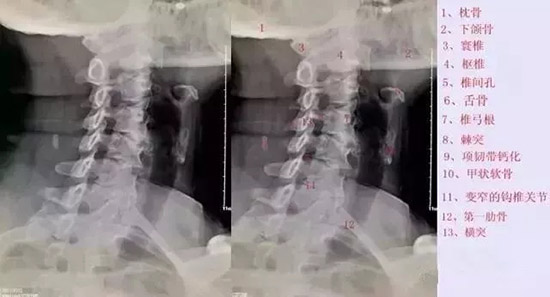

颈椎斜位

拍颈椎双斜位片,主要用来观察椎孔的大小和钩椎关节的骨质增生情况。钩椎关节增生以后,使椎间孔变小,在颈椎斜位片能显示出来,它是产生神经根刺激及椎动脉供血不全的原因。

但是,临床上有些骨质增生明显,并占据椎间孔横径的2/3者也无任何症状。

八孔:指椎间孔。实际上椎间孔是一个短管,故又叫椎间管,只是从X线平片上显示的是"孔"。管内含脊神经的前后根、神经节及节段性动脉、静脉等。主要从斜位片来观察椎间孔的影像变化。正常颈椎间孔呈长方形或椭圆形,高10mm,横径5mm,前后壁光滑。椎间隙变窄可造成椎间孔高度变小。椎间孔前后径变小是钩突增生、关节突增生、关节突关节肥大和椎体滑脱的结果。

如1a图示C4/5间隙狭窄,椎体后缘增生后翘,1b图示C5/6,C6/7双侧钩椎关节增生,椎间孔变窄。

九突:指关节突关节。上位椎体的下关节突及下位椎体的上关节突构成关节突关节。若发生病变,可见关节间隙模糊,关节面粗糙、硬化,关节突关节间隙狭窄(2mm)和边缘骨刺。关节突关节半脱位多与椎体滑脱并存,侧位片上显示上关节突与上位椎体后缘重叠,关节间隙宽窄不一。